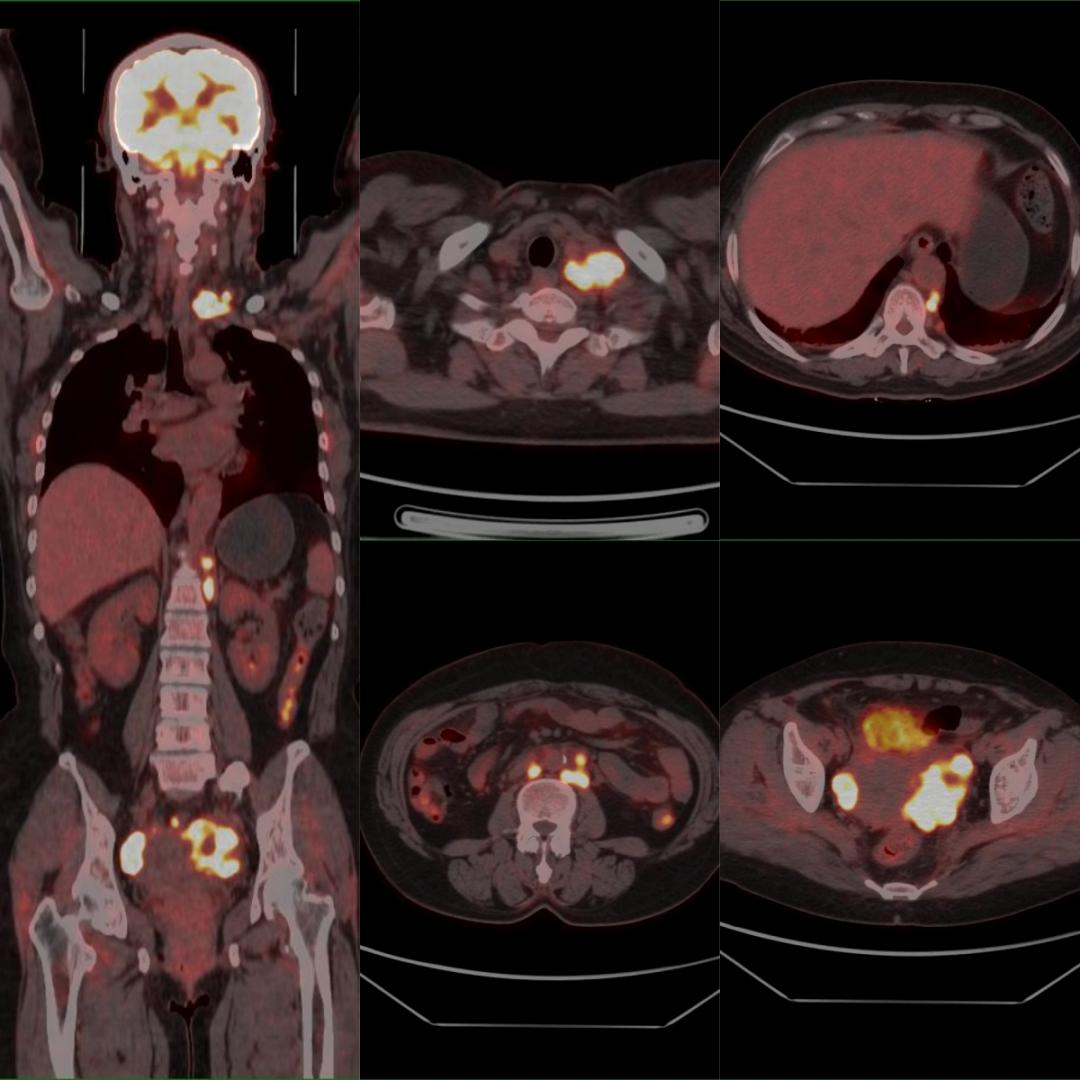

患者以“甲狀腺占位、左鎖骨上占位”入院,行超聲引導(dǎo)下左鎖骨上窩腫物穿刺術(shù),病理:考慮分化差的癌,結(jié)合免疫組化結(jié)果,考慮轉(zhuǎn)移的腺癌,建議檢查乳腺、肺等部位。為明確腫瘤原發(fā)灶,行PET/CT檢查,示:雙側(cè)卵巢、盆腔、腹膜后、后縱隔、左側(cè)鎖骨上多發(fā)高代謝病灶,診斷為雙側(cè)卵巢癌伴多發(fā)淋巴結(jié)轉(zhuǎn)移,后行手術(shù)、化療等治療。

雙側(cè)卵巢Ca伴多發(fā)淋巴結(jié)轉(zhuǎn)移

PET/CT用于卵巢癌淋巴結(jié)轉(zhuǎn)移的術(shù)前評估,其敏感度為83.3%,特異度為98.2%,準確率為95.6%。因此可作為卵巢癌術(shù)前評估淋巴結(jié)轉(zhuǎn)移的重要方法。

本例患者初步診斷左側(cè)鎖骨上淋巴結(jié)不明來源轉(zhuǎn)移癌,臨床選擇PET/CT來尋找原發(fā)灶。PET/CT發(fā)現(xiàn)了非預(yù)期的原發(fā)灶(左側(cè)鎖骨上淋巴結(jié)轉(zhuǎn)移癌最常見的原發(fā)腫瘤并非卵巢,且初步病理提示排查乳腺和肺),大幅縮短了篩查原發(fā)灶的時間,減少了非針對性的檢查,節(jié)約了寶貴的資金,患者得到及時、科學的治療,獲益明顯。